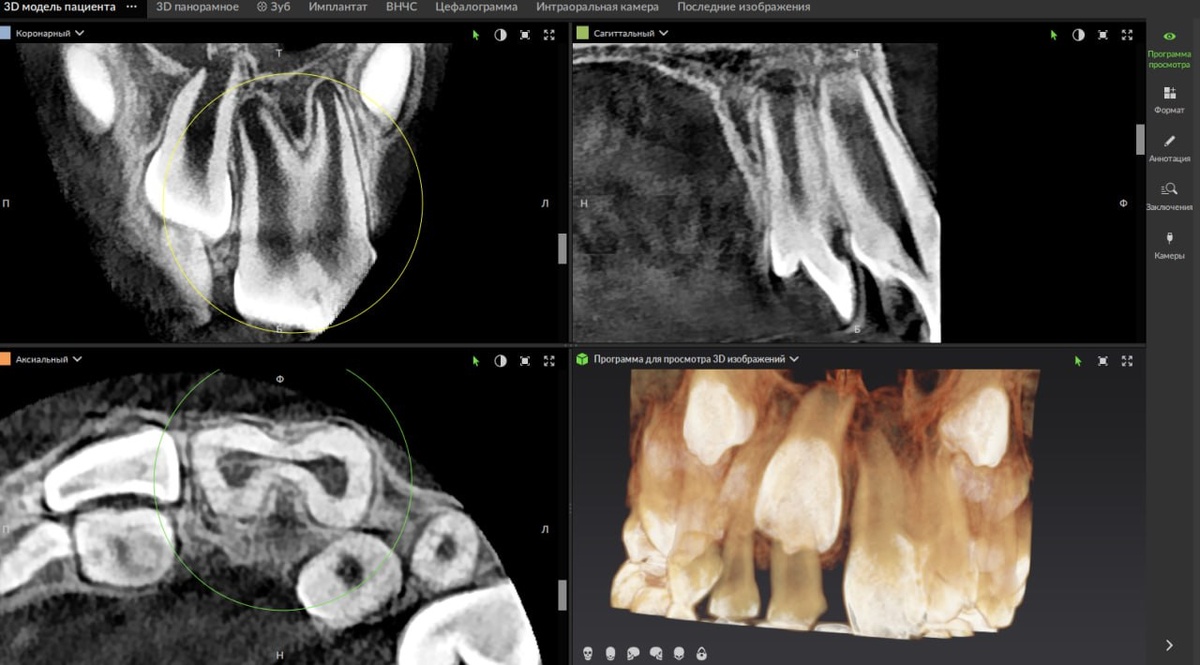

Геминация (удвоение) 2.1 зуба. Клинический кейс

В новом кейсе рубрики «Через призму Х-лучей» разбираем интересное наблюдение от врача-рентгенолога Александра Потапова — случай удвоения зуба 2.1. 🦷

Геминация (удвоение) 2.1 зуба, синоним - шизодонтия (Schizodontia). У данного пациента отмечается неполная геминация (2.1 удвоен, но не образует два отдельных полноценных зуба).

Клиническое значение заключается в повышенном шансе скученности во фронтальном отделе, наличием борозд в коронковой части (зоны, трудно поддающиеся гигиене) и, как следствие, склонности к поражению кариесом. Помимо этого, необычная форма коронки влияет на эстетику в зоне улыбки.